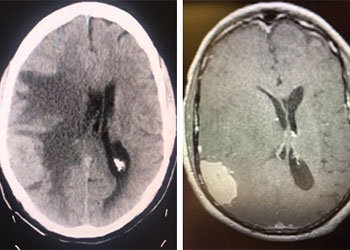

Brain:

Brain Metastasis

Author: Michael Brisman M.D., F.A.C.S., Read More!